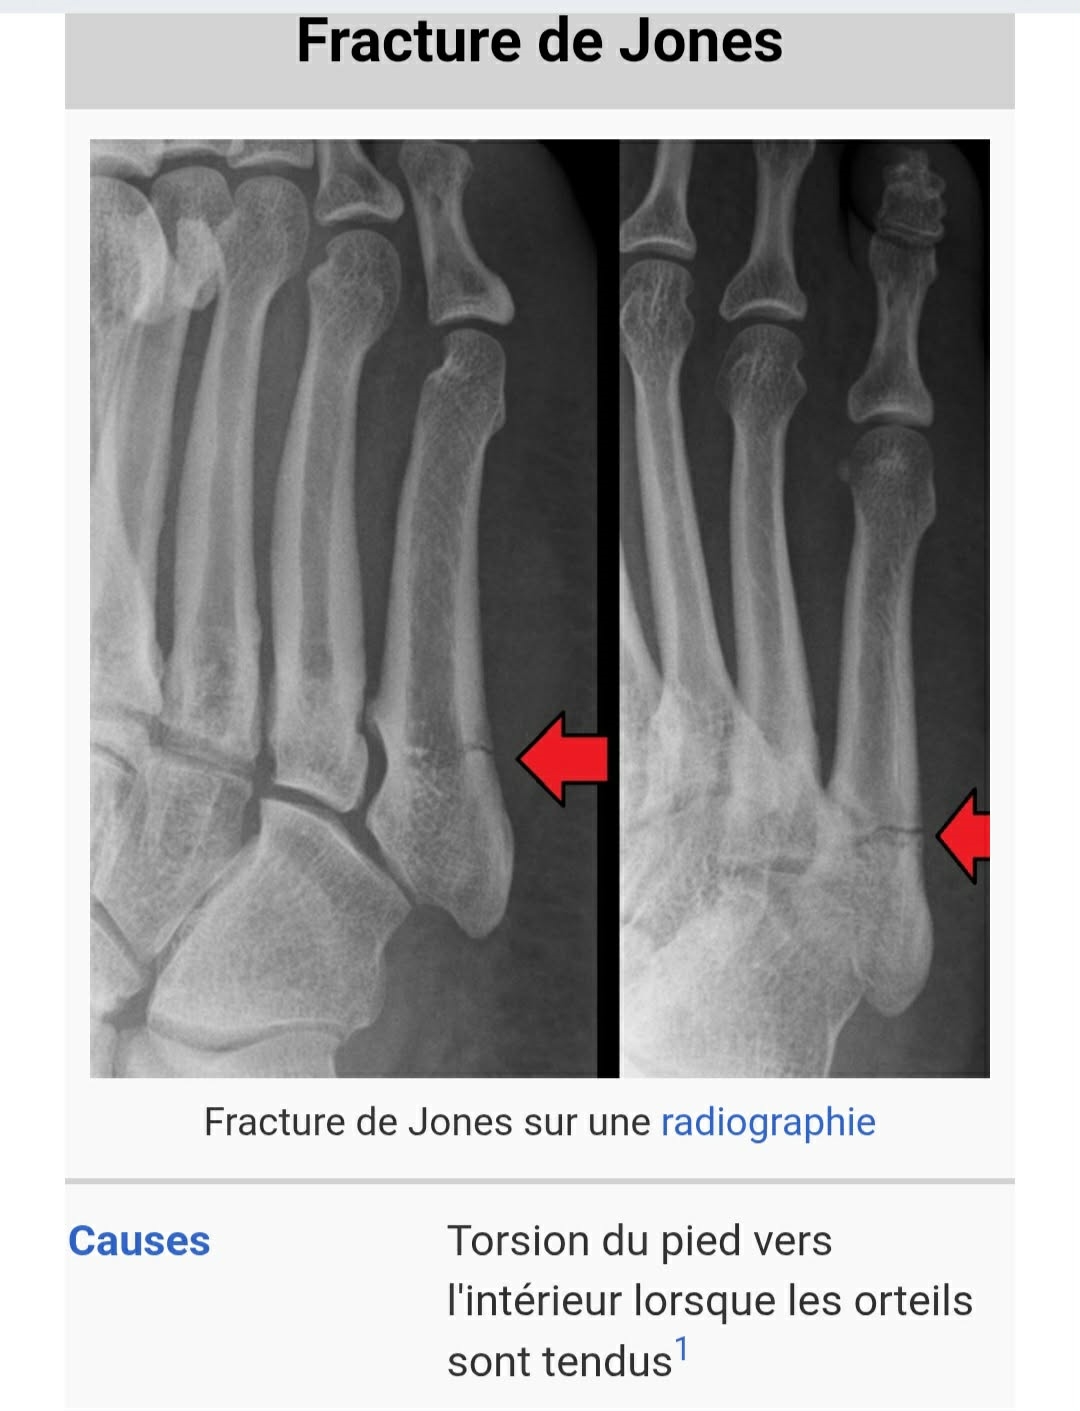

rody83 No pain, no gain | En effet, pas grand chose à voir avec la cheville... d'ailleurs ça me rappelle (toutes proportions gardées, dans mon cas c'était un membre supérieur) ce que je suis fait à la main y'a un an (= broche dans la tête de M5). Par contre il y a fort à parier qu'il lui faudra repasser sur le billard pour enlever la vis... avec une petite indispo associée. Message édité par rody83 le 13-01-2026 à 15:05:06 --------------- .: Passions | Galerie | Blog :. |